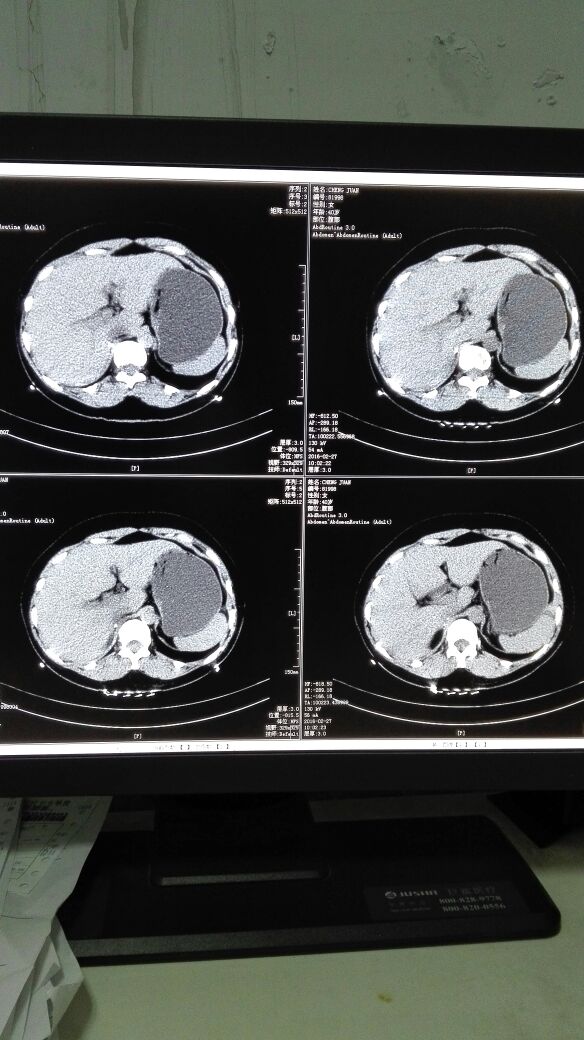

患者女,40岁,医院职工家属。B超体检时发现肝肾间多发囊性占位性病变。行腹部平扫示:右肾上腺区囊性占位,有分割和钙化点,右肾受压下移。诊断意见:右肾上腺囊腺瘤可能性大,建议进一步检查明确。后到市级医院检查并切除手术,病理切片考虑肾上腺囊肿。今腰部不适复查CT片。